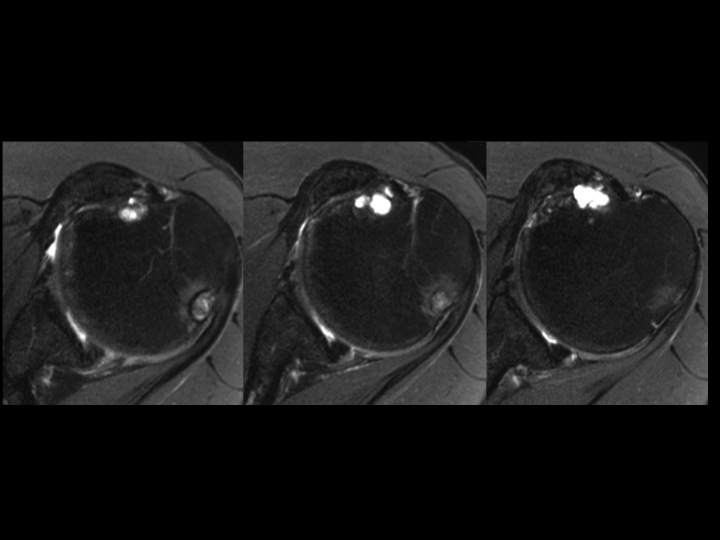

62 yr old male with chronic shoulder pain

It appears that this is more likely to represent an Os Subscapularis than a chronic avulsion fracture non-union of the lesser tuberosity. It seems the ossicle is larger than the normal lesser tuberosity, and the subscapularis tendon appears normal. Cyst-like changes deep to the synchondrosis suggest chronic micromotion. Have any of you seen an Os Subscapularis? Does it exist? I could find no reference. BTW the supra and infra are normal, but there is glenohumeral DJD.

Os Subscapularis vs Old Lesser Tuberosity Avulsion